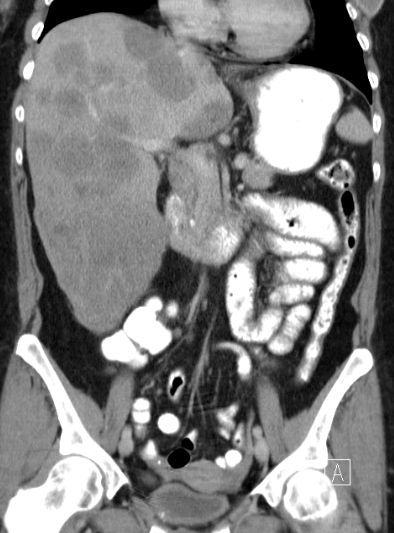

| Lebermetastasen | 51-jährige Patientin mit metastasiertem

Mammakarzinom. Leber vergrößert und von Metastasen durchsetzt.![]() |

46-jährige Frau, die vor 5 Jahren ein

Mammakarzinom hatte. Jetzt ungewöhnliche perihiläre Lebermetastasierung. Bei

der laparoskopischen Sicherung zusätzlich Peritonealkarzinose festgestellt.![]() | |